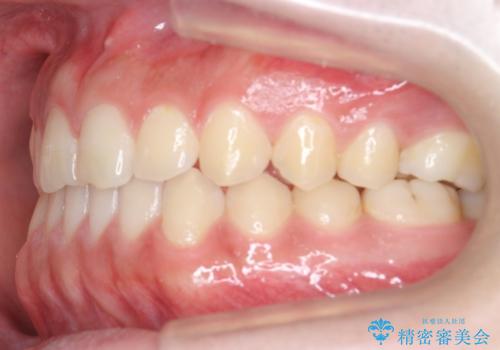

前歯のすきま 受け口 インビザラインで

- 前歯のすき間を気にして来院。

受け口もあり、前歯が端同士であたる、切端咬合となっていました。

下の歯のすき間を閉じて上の歯の内側に入るように位置付けました。

すき間もきれいに閉じ、満足していただきました。

上の前歯は下の歯と直接へりが当たっていた状態(切端咬合)だったため、形がいびつだったのは、わずかにやすりがけをして整えました。